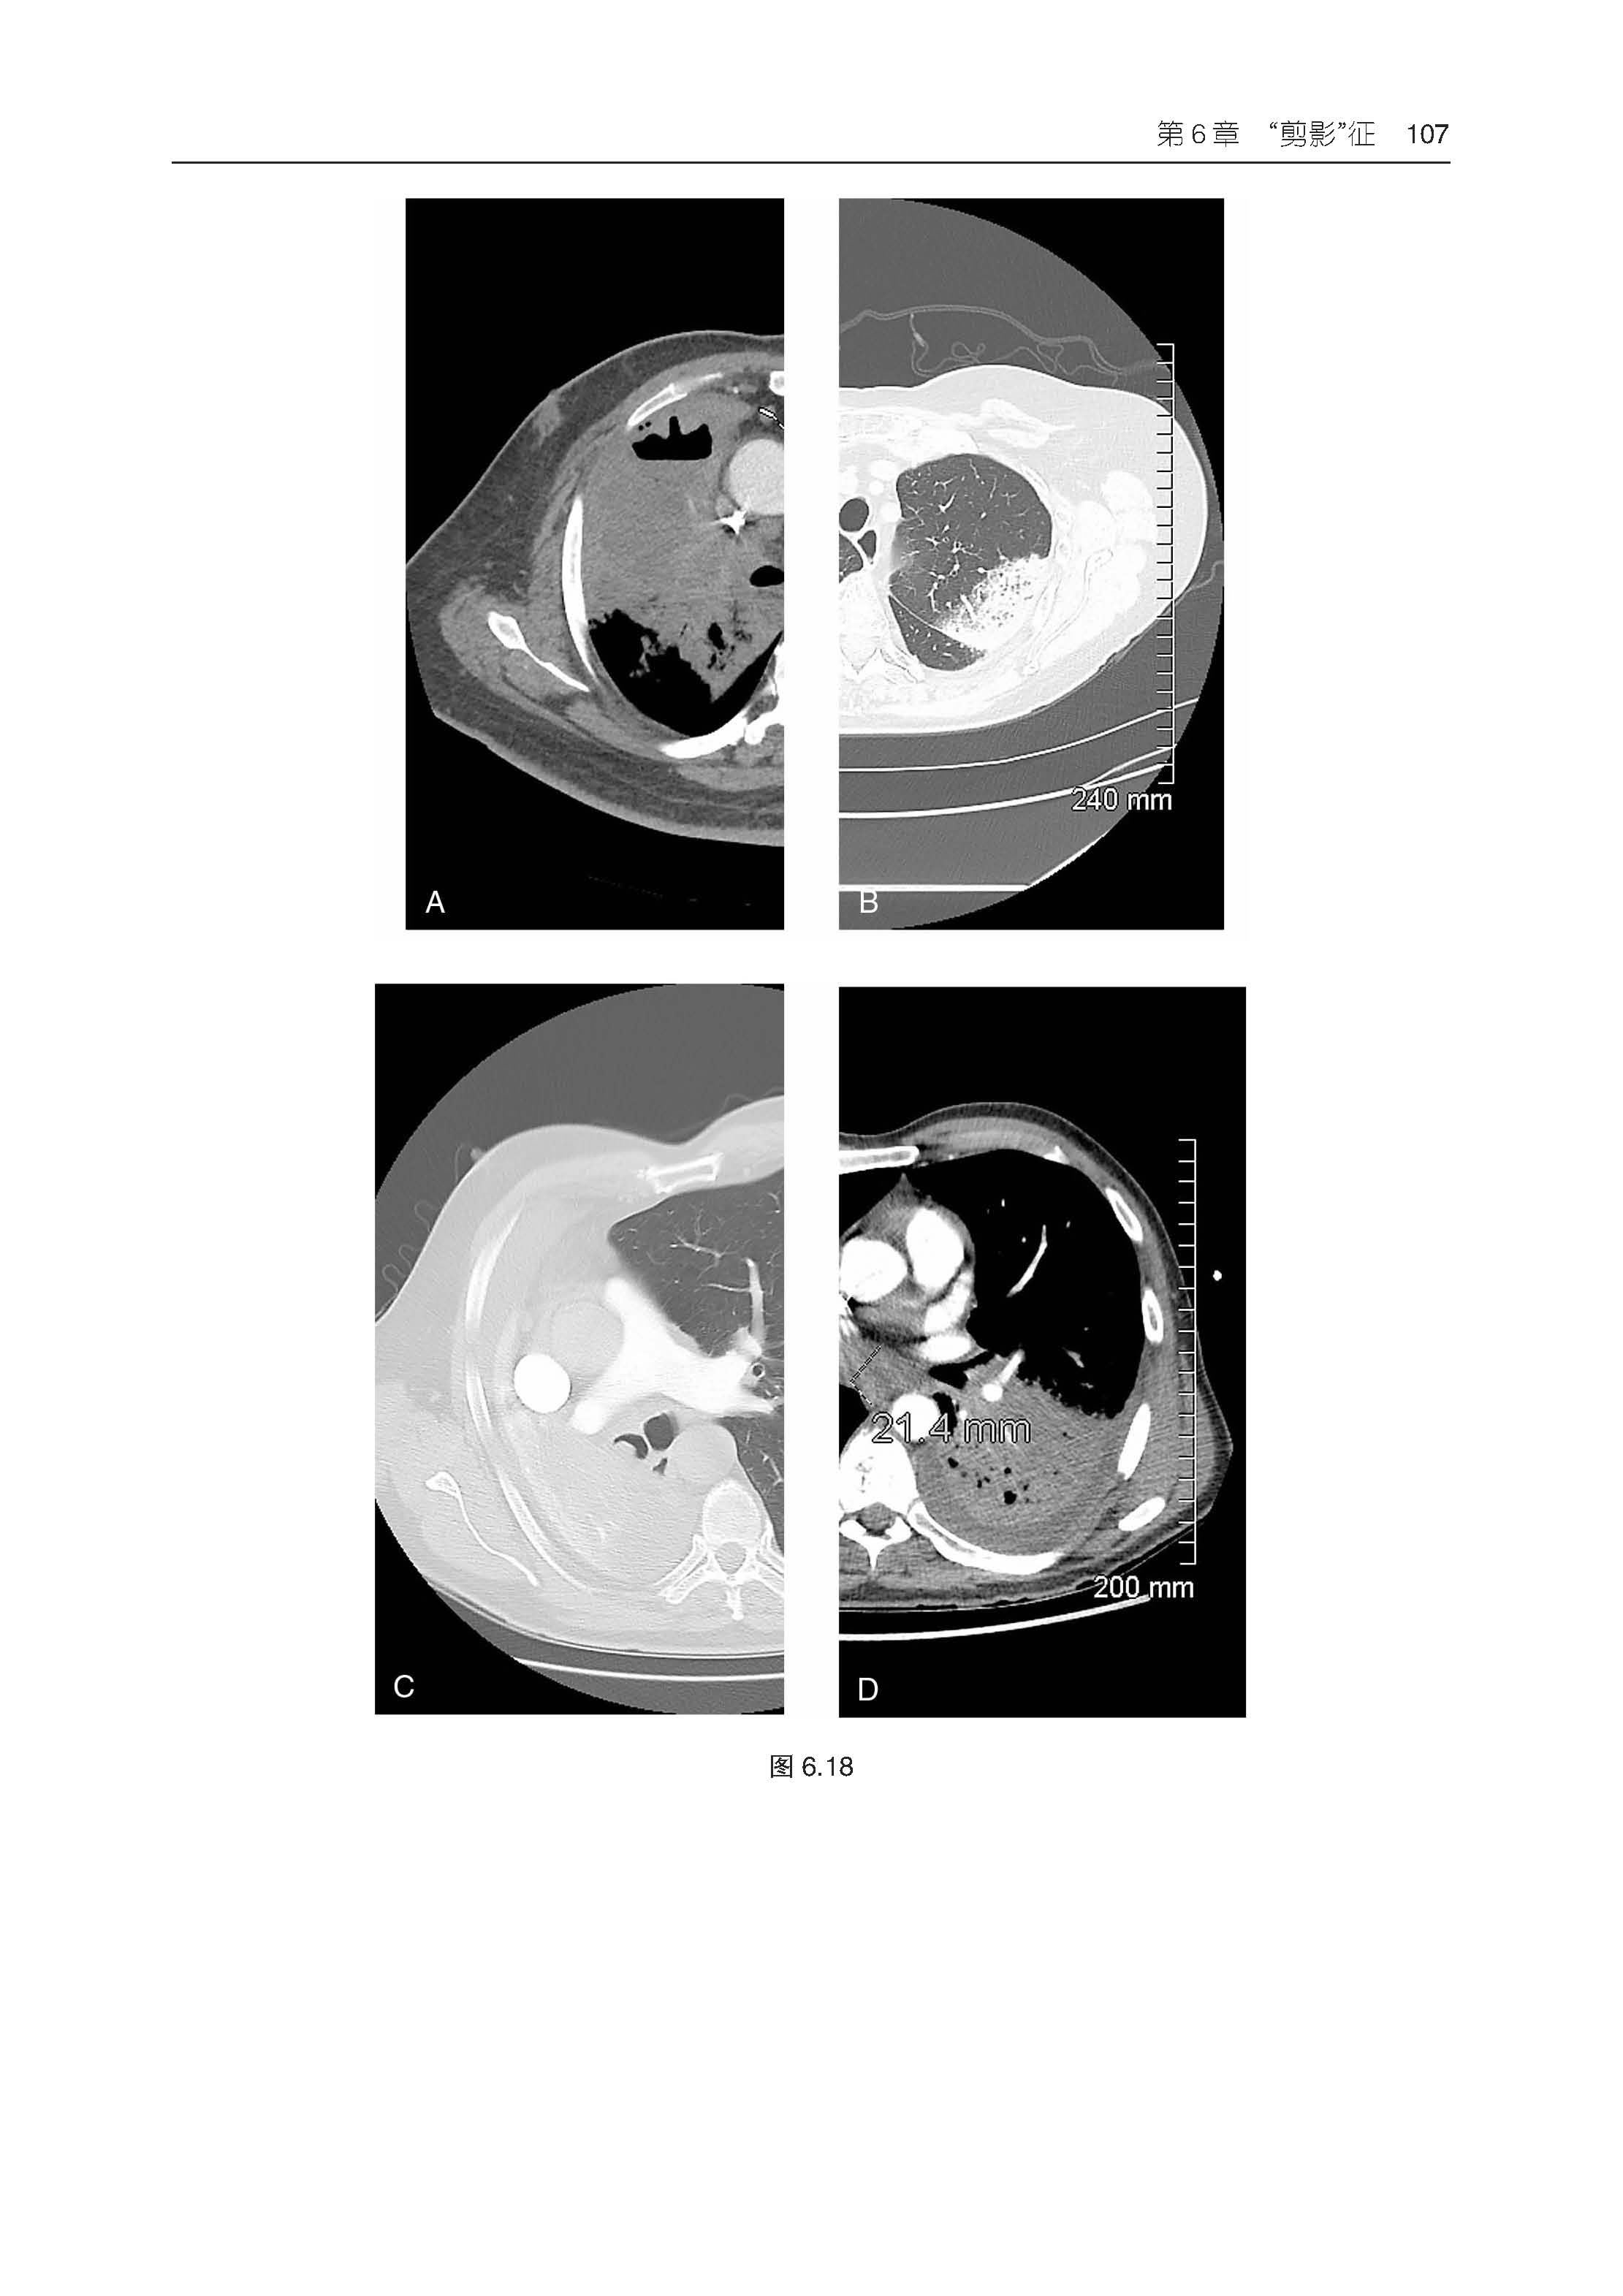

3.包含550 余幅高质量影像图片,并根据需要配有相关的PET、CT 和 MRI 图像。